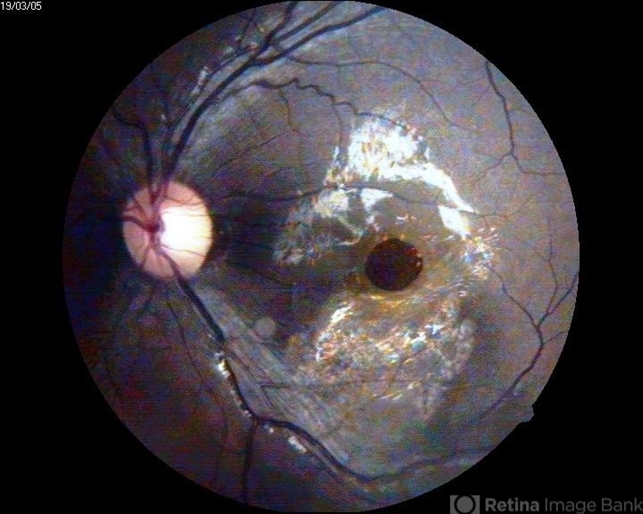

- traumatic macular hole

- 15-year-old boy presented with cricket ball injury.